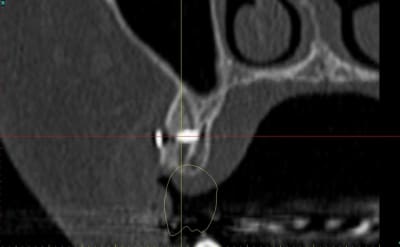

dentiste57 écrivait:

--------------------

> et là ?

> greffe selon ta méthode ?

Cross section dhvkc8 - Eugenol

3d dt3qom - Eugenol

Overview uqcp6u - Eugenol

expansion, c'est plus cool!